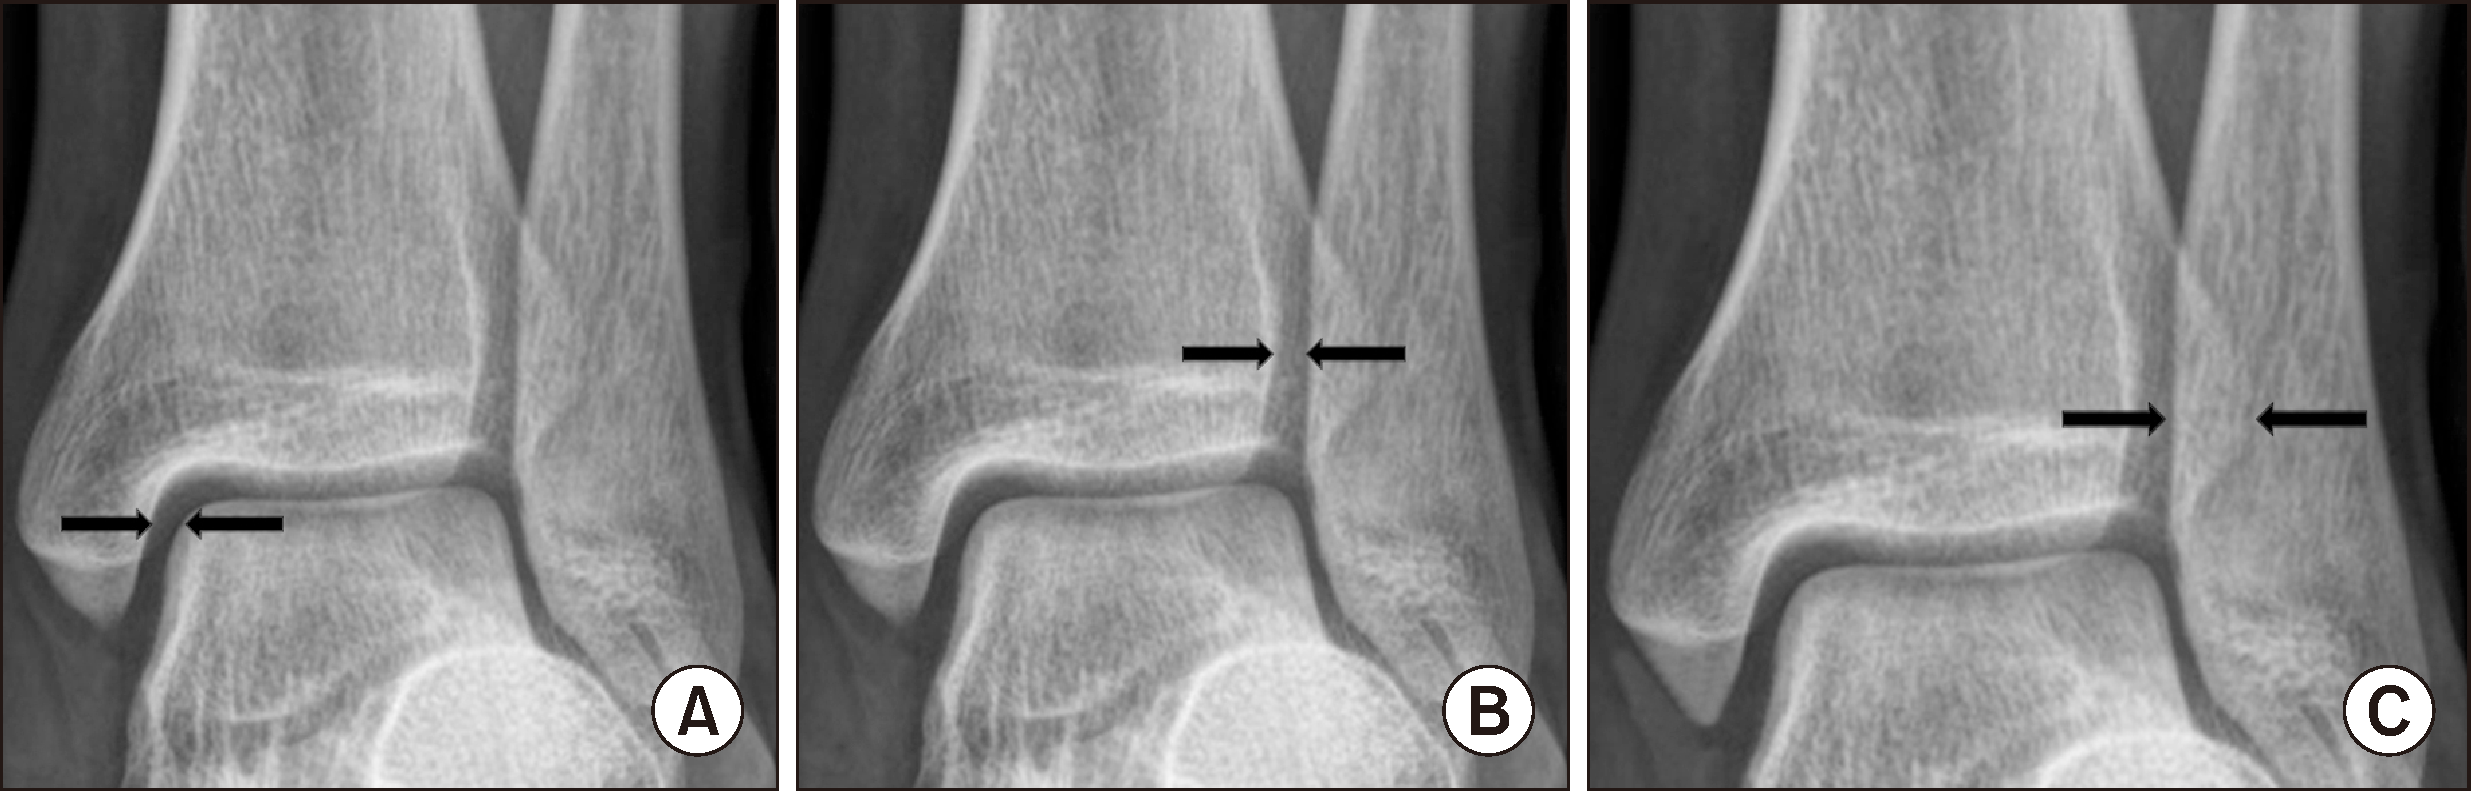

각 수술의 방사선학적 결과를 평가하기 위해 수술 전과 수술 직후 그리고 수술 후 1년이 지난 시점의 발목 전후면 방사선 사진상 경비 간격(tibiofibular clear space)과 경비 겹침(tibiofibular overlap)을 측정하였고 발목 격자 촬영상에서 내측 빈 공간(medial clear space)을 측정하였다. 경비 간격은 비골의 내측 경계와 비골 절흔에 이르는 후과의 외측 경계 사이 거리를 측정하였는데 족관절의 원위 경골 관절면보다 1 cm 근위부에서 측정하였다. 경비 겹침은 외과와 전 경골 결절의 외측면과 겹침으로 경골 관절면 기준 1 cm 근위부에서 측정하였다. 내측 빈 공간은 내과 외측면과 거골의 안쪽 경계면 사이의 간격으로 거골의 천장 위치(dome level)에서 측정하였다(Fig. 2). 수술 전과 수술 직후 그리고 수술 후 1년 뒤의 경비 간격, 경비 겹침, 내측 빈 공간을 측정하여 그 평균값과 표준편차를 구하였다. 측정은 한 명의 정형외과 전공의와 한 명의 정형외과 전문의가 시행하였다. 정형외과 전문의는 1차 측정 후 1주일이 경과한 시점에서 2차 측정을 하였다. 관찰자간과 관찰자내의 측정값의 차이가 있는지를 보기 위하여 짝을 이룬 t-검정을 시행하였으며(Table 1), 급간 내 상관 계수를 구하여 각 측정치의 신뢰의 정도를 평가하였다(Table 2). 연구에는 정형외과 전문의의 측정치를 이용하였다.

Figure 2

Method of measuring medial clear space (A), tibiofibular clear space (B), tibiofibular overlap (C).